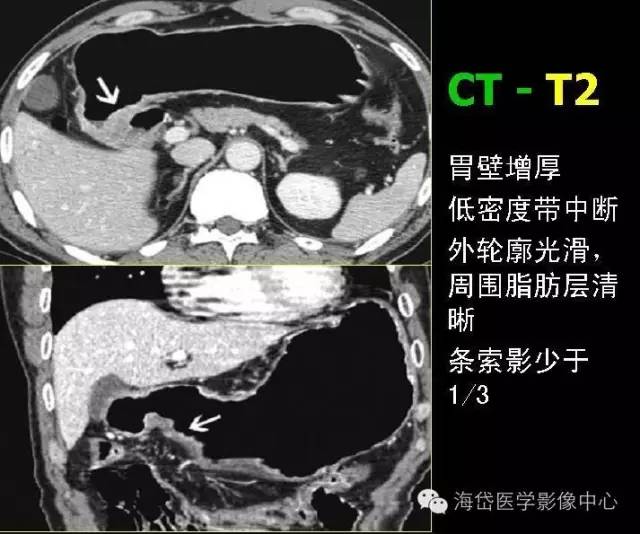

T2:胃壁增厚,低密度帶中斷,外輪廓光滑,周?chē)緦忧逦鷹l索影少于1/3